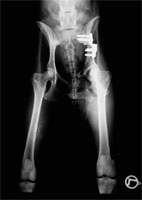

Sechs Wochen postoperativ wird der Hund erneut einer Lahmheitsuntersuchung unterzogen und das Fortschreiten der knöchernen Fusion durch eine Röntgenuntersuchung in tiefer Sedation beurteilt. Gegebenenfalls wird zu diesem Zeitpunkt die zweite Seite operiert (Abb 15). Es zeigt sich in der Regel eine deutliche Kallusbildung an der Osteotomiestelle des Os ilium. Die Manipulation der Articulatio coxae sollte einen guten Grad von Beweglichkeit ergeben. In den besonderen Fällen, bei denen eine 40°-Platte eingesetzt wurde, kann die Abduktion und Extension des Hüftgelenkes ein wenig eingeschränkt sein. Ab Woche 6 sollte mit einem aktiven aufbauenden Bewegungstraining begonnen werden. Auf den besonderen Wert eine Physiotherapie braucht nicht hingewiesen zu werden.

DBO Kontrollröntgen nach 6 Monaten

Abbildung 15: Kontrolle nach 6 Wochen zeigt die Fusion des Os ilium auf der linken Bildseite. Die zweite Seite ist frisch umgestellt.

DBO bilateral Ausheilungsergebnis

Abbildung 17: Ausheilungsergebnis einer bilateralen Dreifachen Beckenosteotomie. Die bisweilen ausbleibende Fusion des Os ischium ist klinisch bedeutungslos.